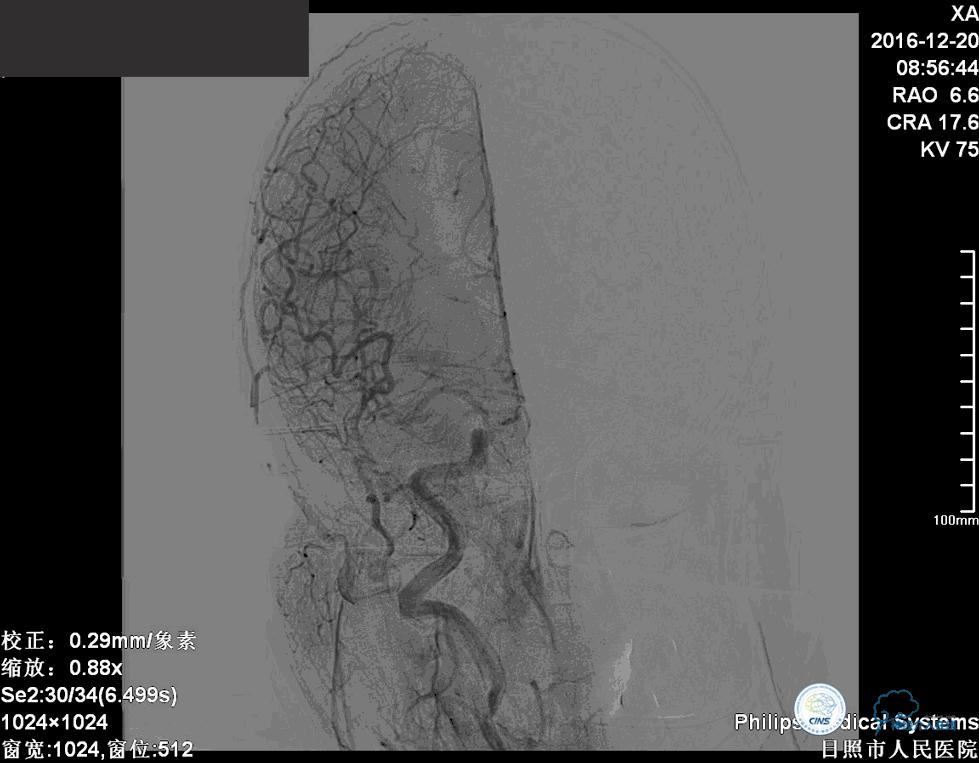

分别选择了7mmx30cm、6mmx30cm、2个4mmx15cm、3mmx8cm、2mmx8mm Target共6个弹簧圈进行栓塞。

术后

术后患者神志清楚,术后肢体运动较术前未见明显异常。

这个手术的难点是在保证动脉瘤致密栓塞的同时,要保证双侧大脑后动脉的通畅。最终手术达到了较好的效果。

术后患者神志清楚,术后肢体运动较术前未见明显异常。双微管技术降低了患者治疗的费用。同时避免了支架置入以后,终生服用抗血小板药物的情况。